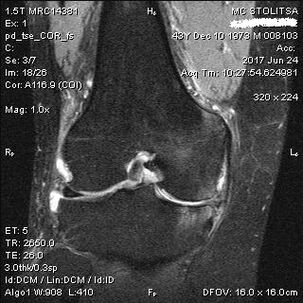

Ang diagnosis ng arthrosis ng kasukasuan ng tuhod ay naganap sa opisina ng isang rheumatologist o orthopedist. Sinusuri ng doktor ang apektadong magkasanib na, palpate ito, nakikinig sa mga reklamo at nagtatanong ng karagdagang mga katanungan. Nagsasagawa ng maraming mga pagsubok - halimbawa, hinihiling sa pasyente na yumuko ang kanyang binti o maglakad ng ilang mga hakbang. Pagkatapos, kung kinakailangan upang linawin ang yugto ng sakit o ang likas na katangian ng mga pagbabago sa pathological, isasangguni ka niya para sa mga karagdagang pag -aaral. Halimbawa, para sa computed tomography o radiography.